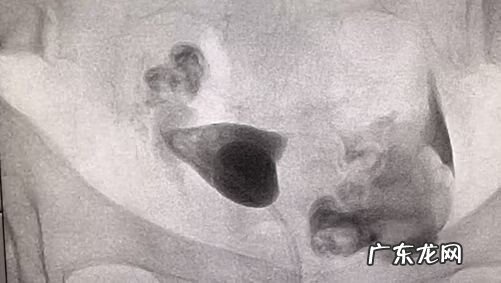

患者 , 28岁 , 结婚1+年 , 性生活正常未孕 , 诊断为:原发性不孕 。造影提示右侧输卵管堵塞 , 介入治疗后已孕28周 。

文章插图